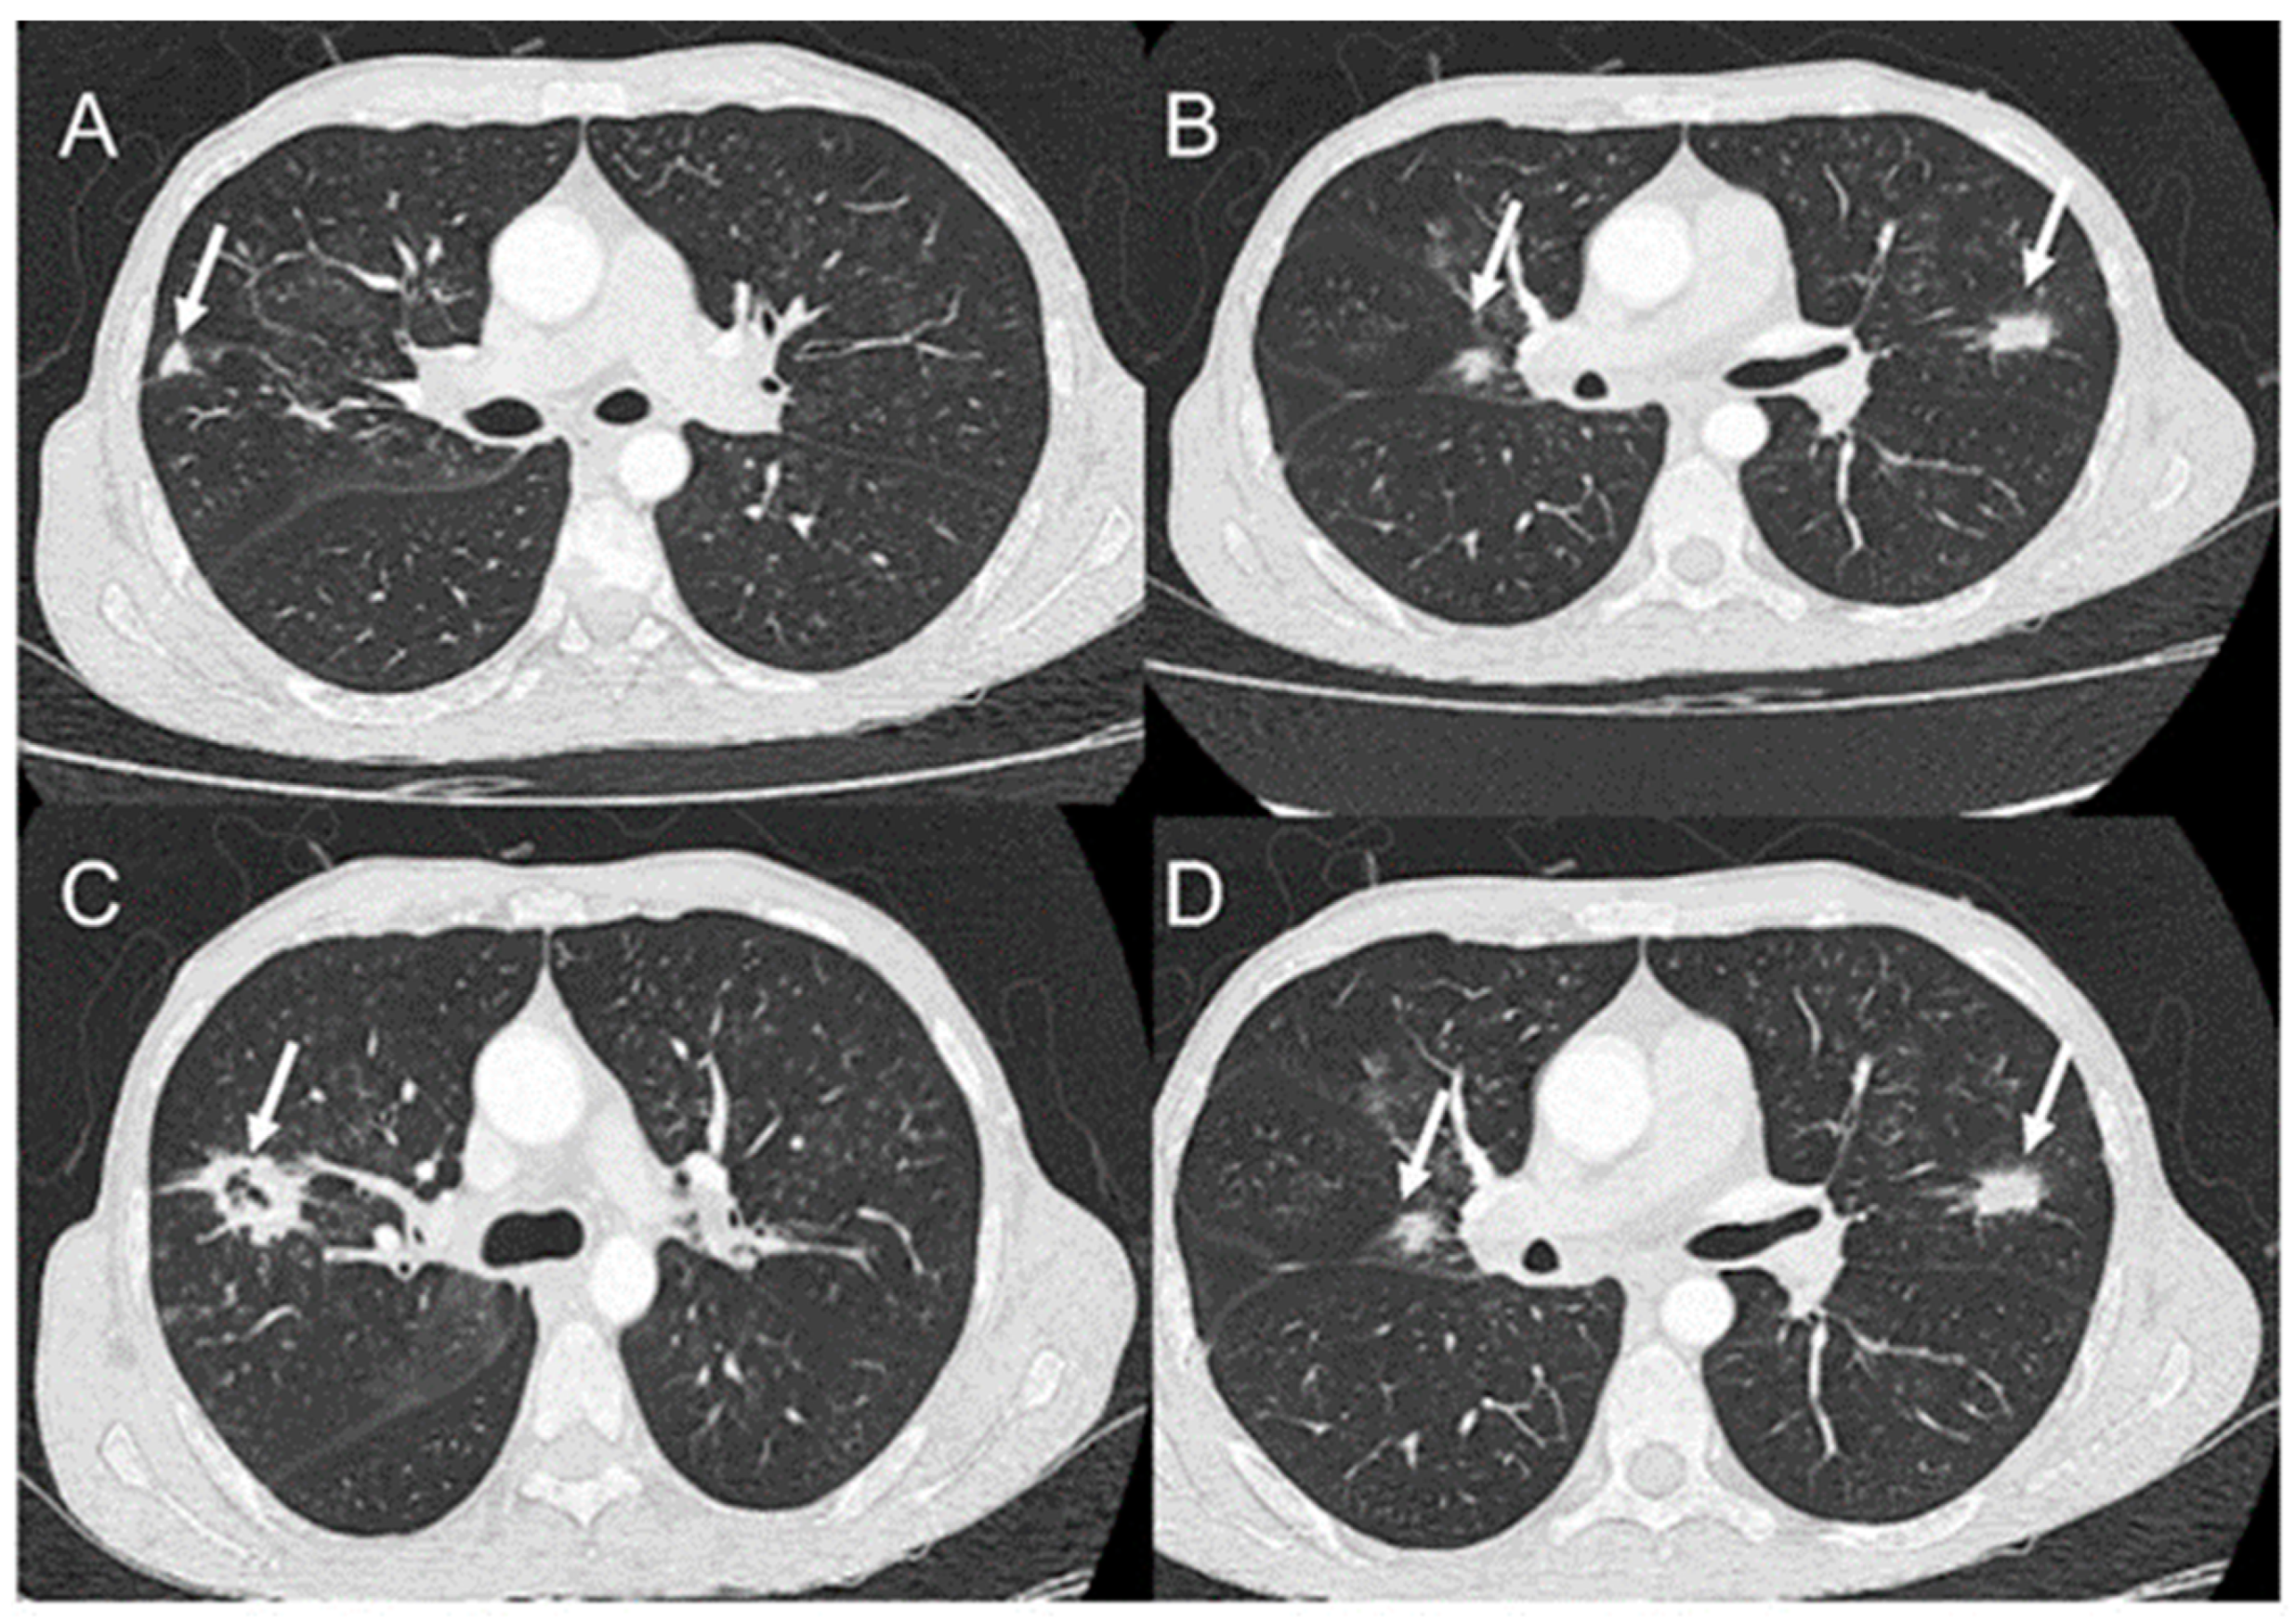

- Rosa Junior, M.; Baldon, I.V.; Amorim, A.F.C.; Fonseca, A.P.A.; Volpato, R.; Lourenco, R.B.; Baptista, R.M.; de Mello, R.A.F.; Pecanha, P.; Falqueto, A. Imaging paracoccidioidomycosis: A pictorial review from head to toe. Eur. J. Radiol. 2018, 103, 147–162. [Google Scholar] [CrossRef]

- Queiroz-Telles, F.; Escuissato, D.L. Pulmonary paracoccidioidomycosis. Semin. Respir. Crit. Care Med. 2011, 32, 764–774. [Google Scholar] [CrossRef]

- Queiroz-Telles, F.V.; Pecanha Pietrobom, P.M.; Rosa Junior, M.; Baptista, R.M.; Pecanha, P.M. New Insights on Pulmonary Paracoccidioidomycosis. Semin. Respir. Crit. Care Med. 2020, 41, 53–68. [Google Scholar] [CrossRef]